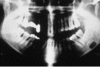

Befunde dieses RÖ-Bild

Panoramaschichtaufnahme. Zystischer Prozess im Unterkiefer links im Bereich der Schaltlücke in regio 36 ohne Lagebeziehung zum Zahnbestand.

Histologie: radikuläre Zyste. Diagnose: Residualzyste [nach Zahn- Extraktion]

Panoramaschichtaufnahme.

Zystischer Prozess im Unterkiefer links mit

Lagebeziehung zum wurzelgefüllten Zahn 37.

Histologie: radikuläre Zyste